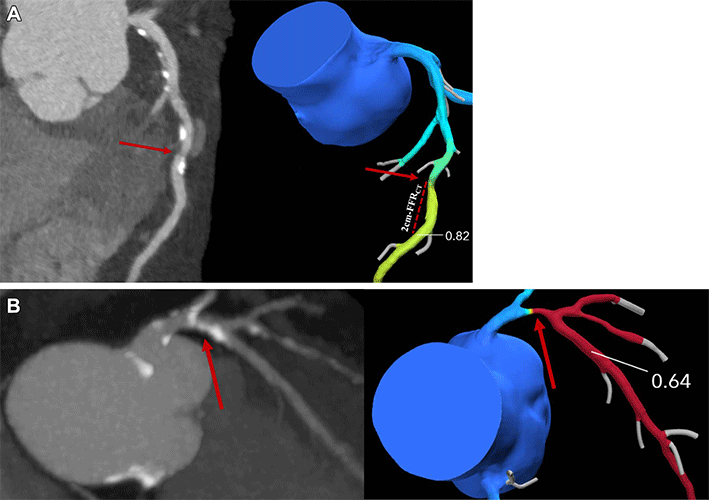

Coronary CT angiography (CTA) images (left side, A and B) and corresponding derived fractional flow reserve (FFR) (right side, A and B). The location 2-cm distal to stenosis is manually delineated and the coronary CTA–derived FFR (FFRCT) value is registered. The lowest lesion-specific coronary CTA–derived FFR value is used to categorize participants, with (A) greater than 0.80 representing a normal value and (B) 0.80 or less representing an abnormal value.